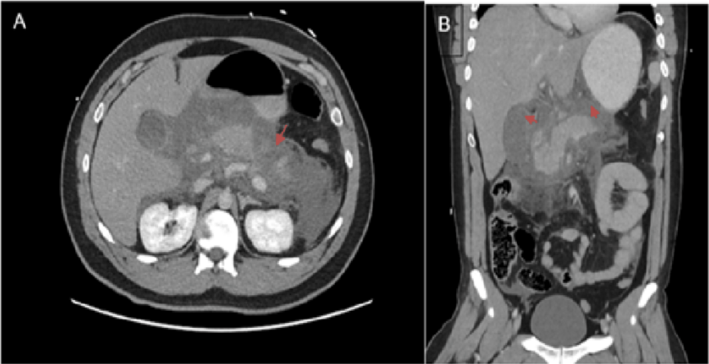

Fasciotens®Abdomen system application for delayed primary fascial closure and observed physiological improvement of the patient

fasciotens®Abdomen was used in a middle-aged patient with severe peritonitis after small bowel perforation.